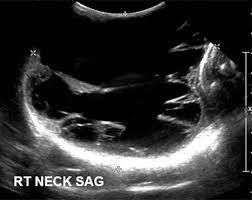

An ultrasound of the thyroid produces pictures of the thyroid gland and the adjacent structures in the neck. The scan is painless and only takes a few minutes. It can detect abnormal tissues, growths, and cysts and give a suspicion of cancer based on how those images look. Confirming that a lump in the neck is developing from the thyroid or connected tissue. Doctors and pathologists do not use internal ultrasound scan frequently to detect lymphoma. Ultrasound guidance is used to perform thyroid biopsies and improves the diagnostic accuracy of fine needle biopsy. The first lymph node cancer cells spread to is known as the sentinel node. Ultrasounds can't show lung cancer or bone cancer. Some of the indications for thyroid or neck ultrasound are thyroid nodules, goiter, thyroid cancer and other neck masses. For neck or thyroid mass see ent. To see whether the cancer has spread, some or all of the lymph nodes are removed and checked for cancerous cells. Fna might also be used in patients whose cancer has been treated by surgery and/or radiation therapy , to help find out if a neck mass in the treated area is scar tissue or if it's a return (recurrence) of the cancer. The lymph nodes in the neck are often the first place cancer cells spread to outside the primary site.

Figure 1 From Post Thyroidectomy Neck Ultrasonography In Patients With Thyroid Cancer And A Review Of The Literature Semantic Scholar from d3i71xaburhd42.cloudfront.net I have ocd and my obsession of 30 years is that i have a tumor on in my throat or neck. Additionally, how do they test for thyroid cancer? An ultrasound scan of the neck uses sound waves to build up a picture of your neck and lymph nodes. Ultrasounds can't show lung cancer or bone cancer. The diagnosis of papillary thyroid cancer is made with an ultrasound guided small sampling of cells from the thyroid gland or neck lymph nodes (or both in some instances). Our doctors also use ultrasound to check lymph nodes in the neck, where some forms of thyroid cancer can spread. For most types of cancer, a biopsy is the only sure way for the doctor to know if an area of the body has cancer. We prospectively studied 19 patients referred to the institut gustave.

While it can't diagnose cancer, it can detect the abnormal tissues that may possibly be cancerous. Ultrasound is often one of the first line tests in the detection of cancer. For neck or thyroid mass see ent. Lymph nodes are part of the lymphatic system, which helps to protect us from infection and disease. Some of the indications for thyroid or neck ultrasound are thyroid nodules, goiter, thyroid cancer and other neck masses. Ultrasound imaging is a noninvasive medical test that helps physicians diagnose and treat medical conditions. Part of the throat (cancers of the oropharynx and tonsils, nasopharynx and hypopharynx) the nose or sinuses (nasal and sinus cancer) the salivary glands. Ultrasound guidance is used to perform thyroid biopsies and improves the diagnostic accuracy of fine needle biopsy. Sonography has an accuracy rate of about … Fna might also be used in patients whose cancer has been treated by surgery and/or radiation therapy , to help find out if a neck mass in the treated area is scar tissue or if it's a return (recurrence) of the cancer. If the person has a lump in the neck, an fna can show if the mass is from cancer spread. It can be used with a fine needle aspiration test or core biopsy test to accurately direct the tip of the needle into the lump. It can detect abnormal tissues, growths, and cysts and give a suspicion of cancer based on how those images look.